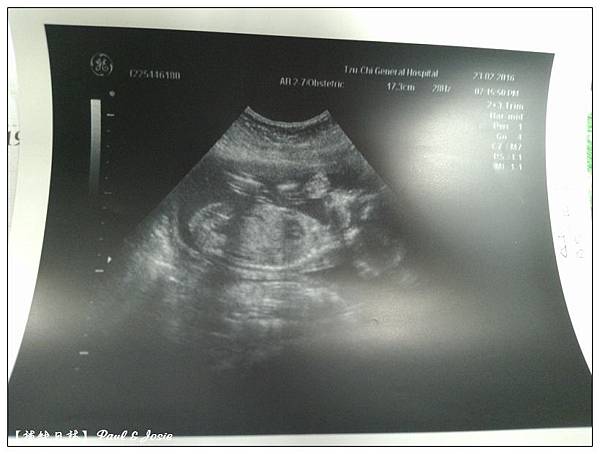

2016/02/23 第四次產檢 19w+5d 女寶寶頭骨橫徑4.89cm,450g 。

2016/03/22第五次產檢 23w+4d 女寶寶頭骨橫徑5.64cm,680g 。